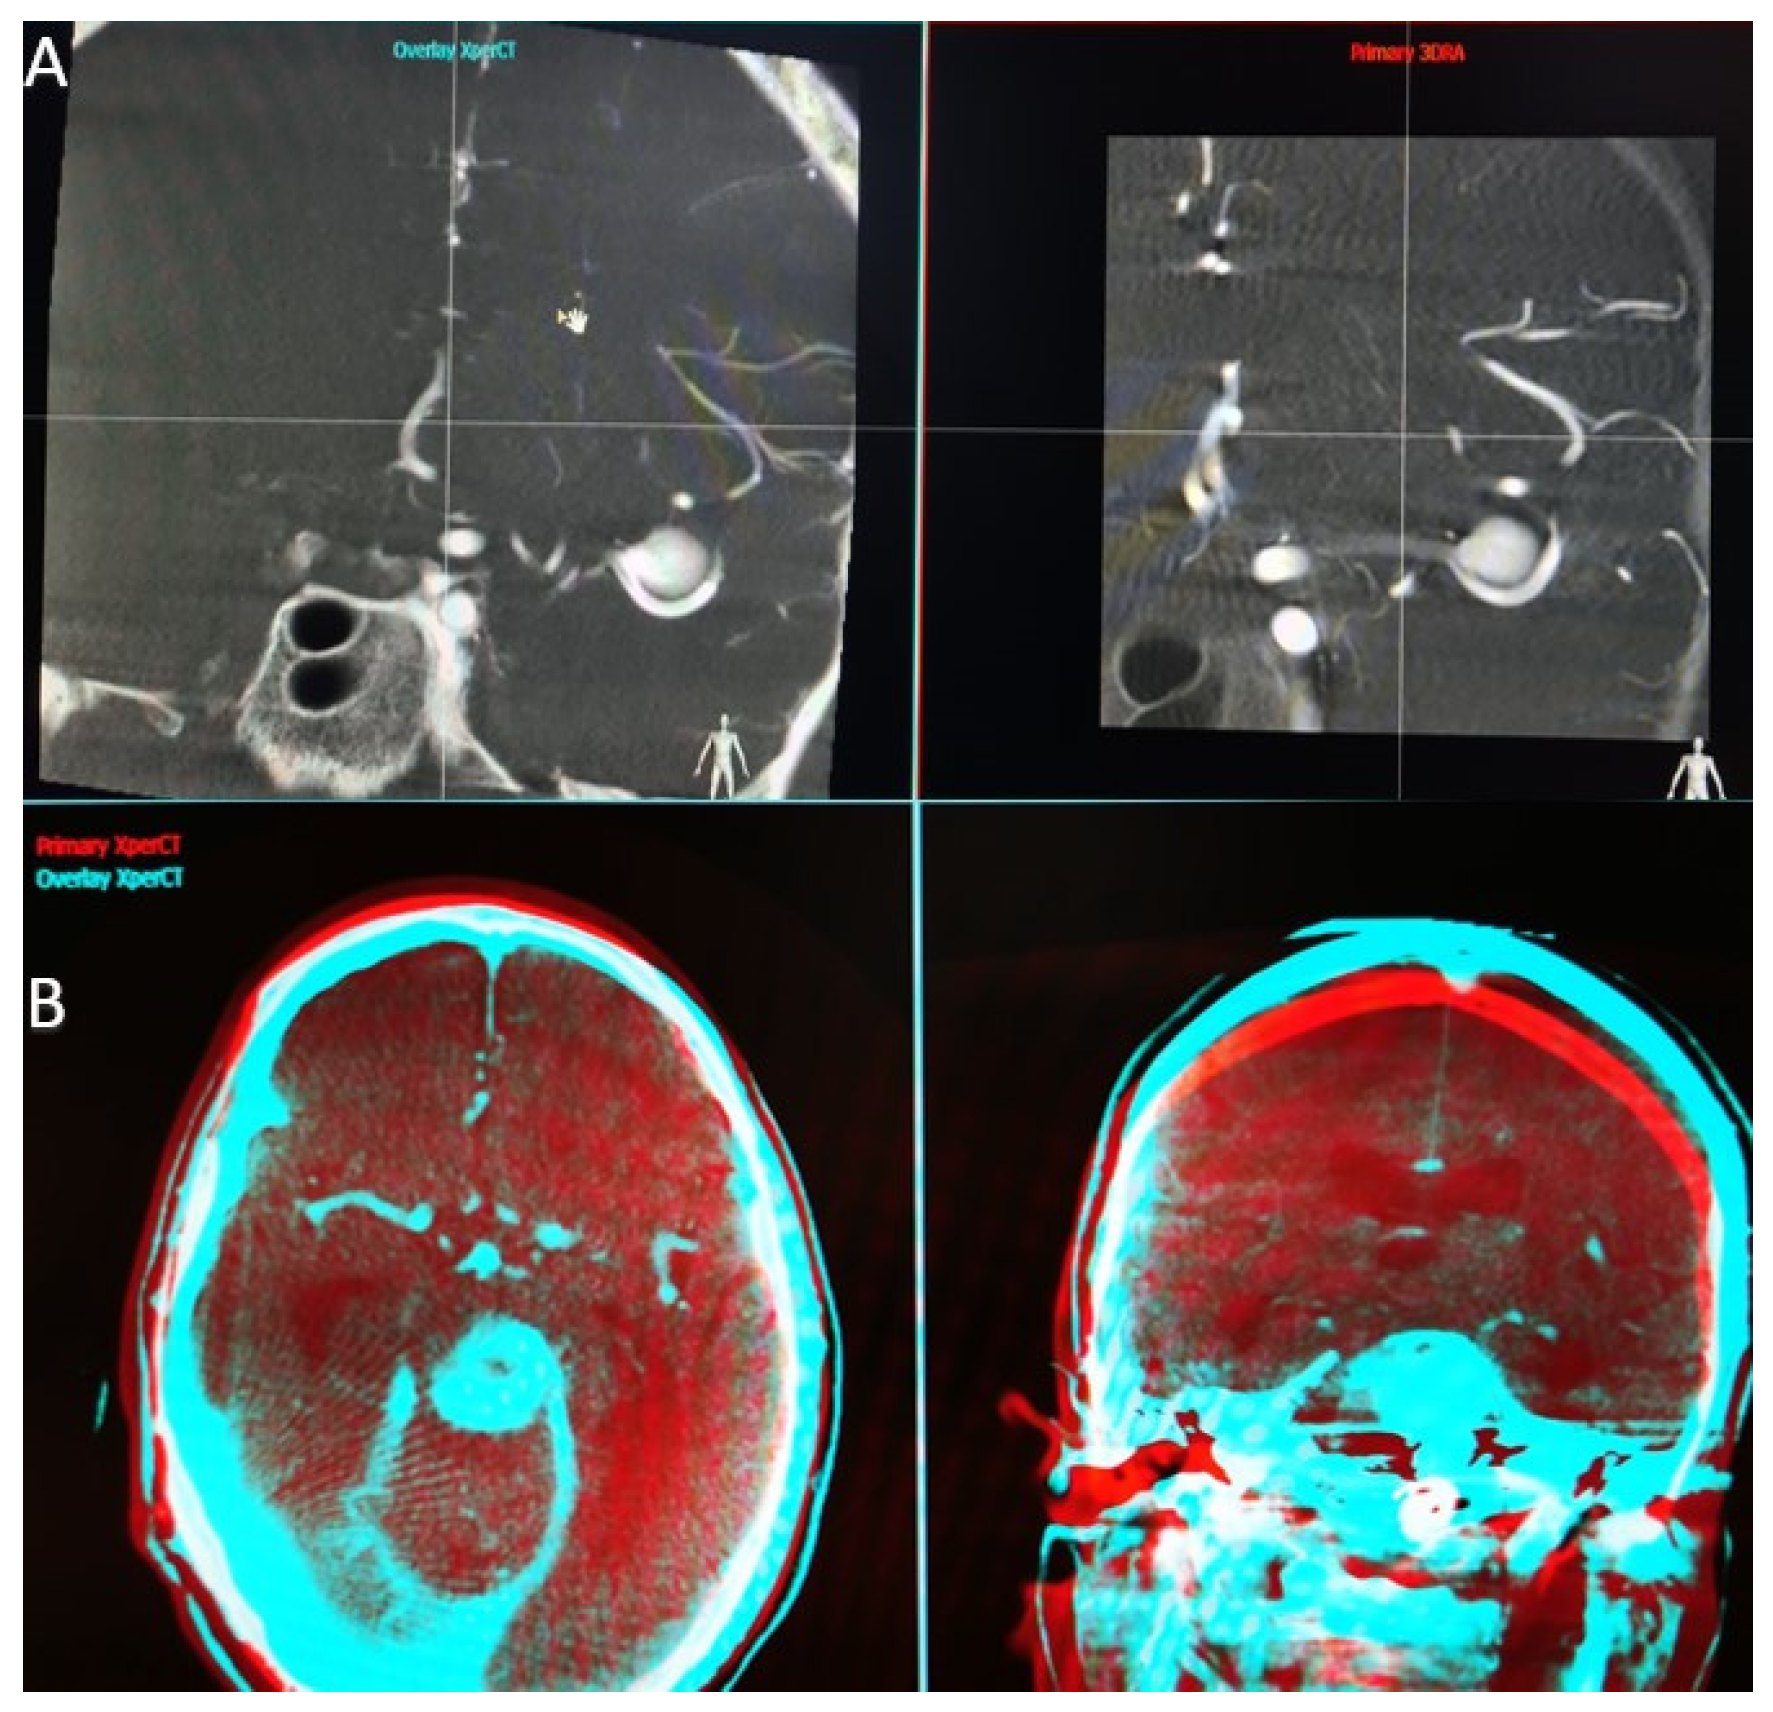

When the application that performs the overlay function is launched, we find a first interface that parallels the two volumes we have selected (Figure 1A). At this step, we have to choose a high Hounsfield unit object landmark (bone, endosaccular device, stent, coils) that we use to synchronize the volumes in all 3 planes (axial, sagittal, and coronal). Once the target point is placed in the same incidence on both volumes and in all 3 planes, we can open the second interface.

Figure 1.

(A) Workstation first interface that parallels the two volumes we have selected. (B) Workstation second interface, red—primary volume, and blue—overlay volume, two spatial planes at the same time.

In the second interface (Figure 1B), the screen is also split into two parts, and we have the possibility to analyze the superposition of the two volumes in different colors (red—primary volume, and blue—overlay volume) and in two spatial planes at the same time. Both volume images were presented in different colors and in the same window as the orthogonal multi-planar reconstruction (MPR) images in axial, sagittal, and coronal orientations. We can now manually correct angulation errors (higher in patients without general anesthesia) and accurately calibrate the anatomy, thereby compensating for vascular anatomical changes due to stent placement.

The automatic overlay function is more efficient in cases where the spatial landmarks were selected manually in the first interface, as it avoids large mismatches that cannot be fully compensated by the automatic software.